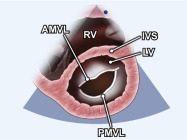

| 2.11. Mặt cắt trục ngắn cạnh ức (ngang mức van hai lá) |

||||||||

|

|

Cửa sổ siêu âm cạnh ức

Mặt cắt trục ngắn cạnh ức Từ vị trí các đại động mạch gập đầu dò xuống dưới |

Thất phải (RV) Vách liên thất (IVS)

Lá trước van hai lá (AMVL) Lá sau van hai lá (PMVL) Thất trái (LV) |

|||||